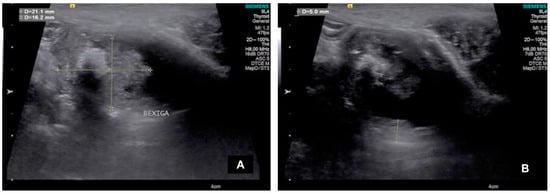

| Dog | Height (cm) | Length (cm) | Echotexture | Echogenicity | Location |

|---|---|---|---|---|---|

| 1 | 0.88 | 3.53 | Heterogeneous | Mixed | Dorsal |

| 2 | 2.76 | 4.49 | Heterogeneous | Hyperechogenic | Ventral, trigone e prostatic urethra |

| 3 | 1.62 | 2.11 | Heterogeneous | Hyperechogenic | Cranial (ventrodorsally) |

| 4 | 3.75 | 3.63 | Heterogeneous | Mixed | Cranial (ventrodorsally) |

| 5 | 0.60 | 1.41 | Homogeneous | Hyperechogenic | Trigone |

| 6 | 1.24 | 2.51 | Heterogeneous | Hyperechogenic | Dorsal |

| 7 | 1.19 | 3.87 | Heterogeneous | Hyperechogenic | Ventral |